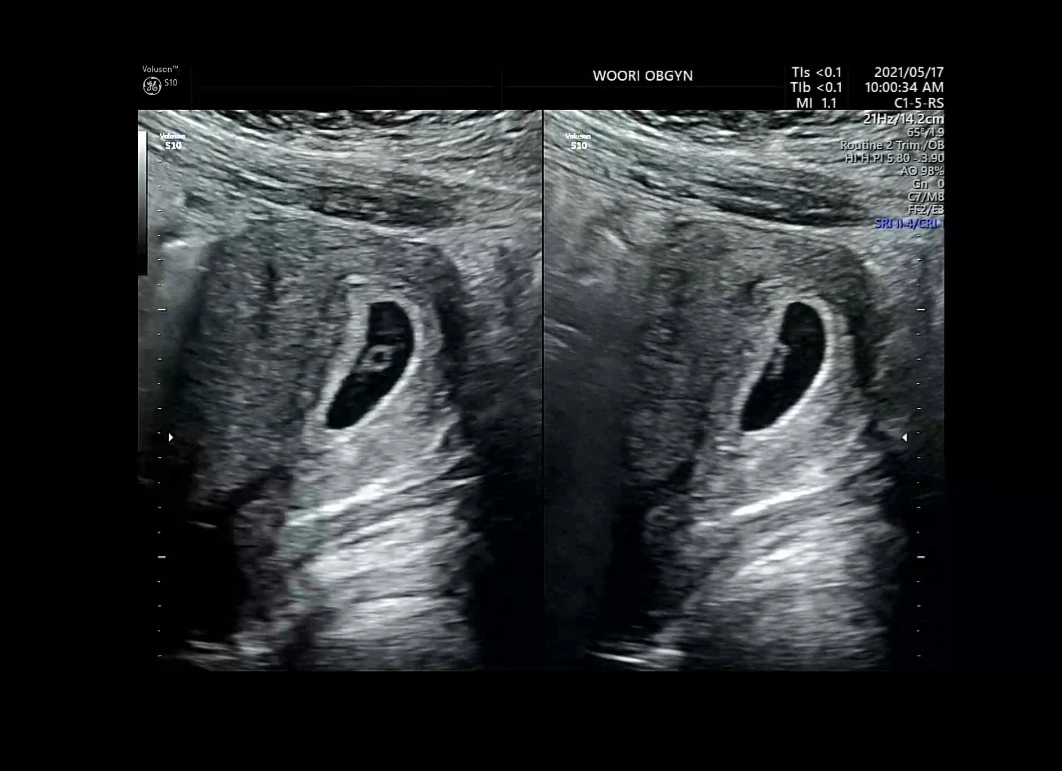

2주 전에 보던 콩알이는 온데간데없고 강낭콩이 떡하니 보여서 깜짝 놀랐다.

우리아가는 2주만에 강낭콩이되었다.

“우리 아이는 정확히 6주 차가 맞네요. 생리일수가 너무 늦어져서 더 된 줄 알았는데 6주입니다.

그 전보다 아주 잘 커서 자리까지 잘 잡았네요. 보이시죠?”

“이 강낭콩처럼 보이는 부분 안에 이 작은 하얀 부분이 우리 아이예요. 음~ 심장소리가 들릴 거 같아요. 잠시만요.”

“심장소리가 120 이하면 유산의 가능성이 있는데, 우리 아가는 120이 넘어가네요. 아주 잘 크고 있다는 증거죠.”